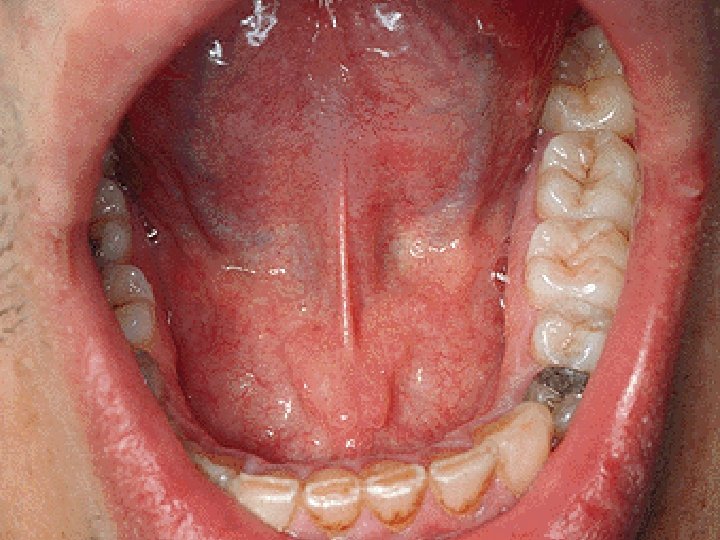

CAVUM ORIS PROPRIUM

PALATUM Glandulae palatinae Aa. palatinae majores et minores A. palatina ascendens A. pharyngea asc. Nn. palatini minores et majores Plexus pharyngeus N. nasopalatinus Nll. submandibulares Nll. cervicales prof.

TONSILLA PALATINA Fossa tonsillaris Plica semilunaris Fossa supratonsillaris Plica triangularis

Ductus submandibularis N. lingualis Ggl. submandibulare A. et v. lingualis N. hypoglossus

N. lingualis N. glossopharyngeus (CN IX) N. hypoglossus (CN XII) A. lingualis